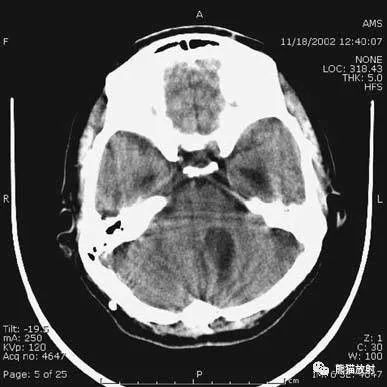

1、颅底层面眦耳线层面

颅前窝底部:眼眶、眼球、筛窦、蝶窦、前床突等。

颅中窝:前界——蝶骨;后界——颞骨岩部(岩骨);内缘——海绵窦及垂体窝;外缘——颞骨,窝内为颞叶,其内侧为海马回。

颅后窝:前缘——岩骨;后缘——枕骨;鞍背后方——脑桥前池,向两侧延伸为脑桥小脑角池。

第四脑室:位于颅后窝中线上,后面紧邻小脑蚓部,其两侧为小脑扁桃体。

延髓、脑桥:位于第四脑室前。